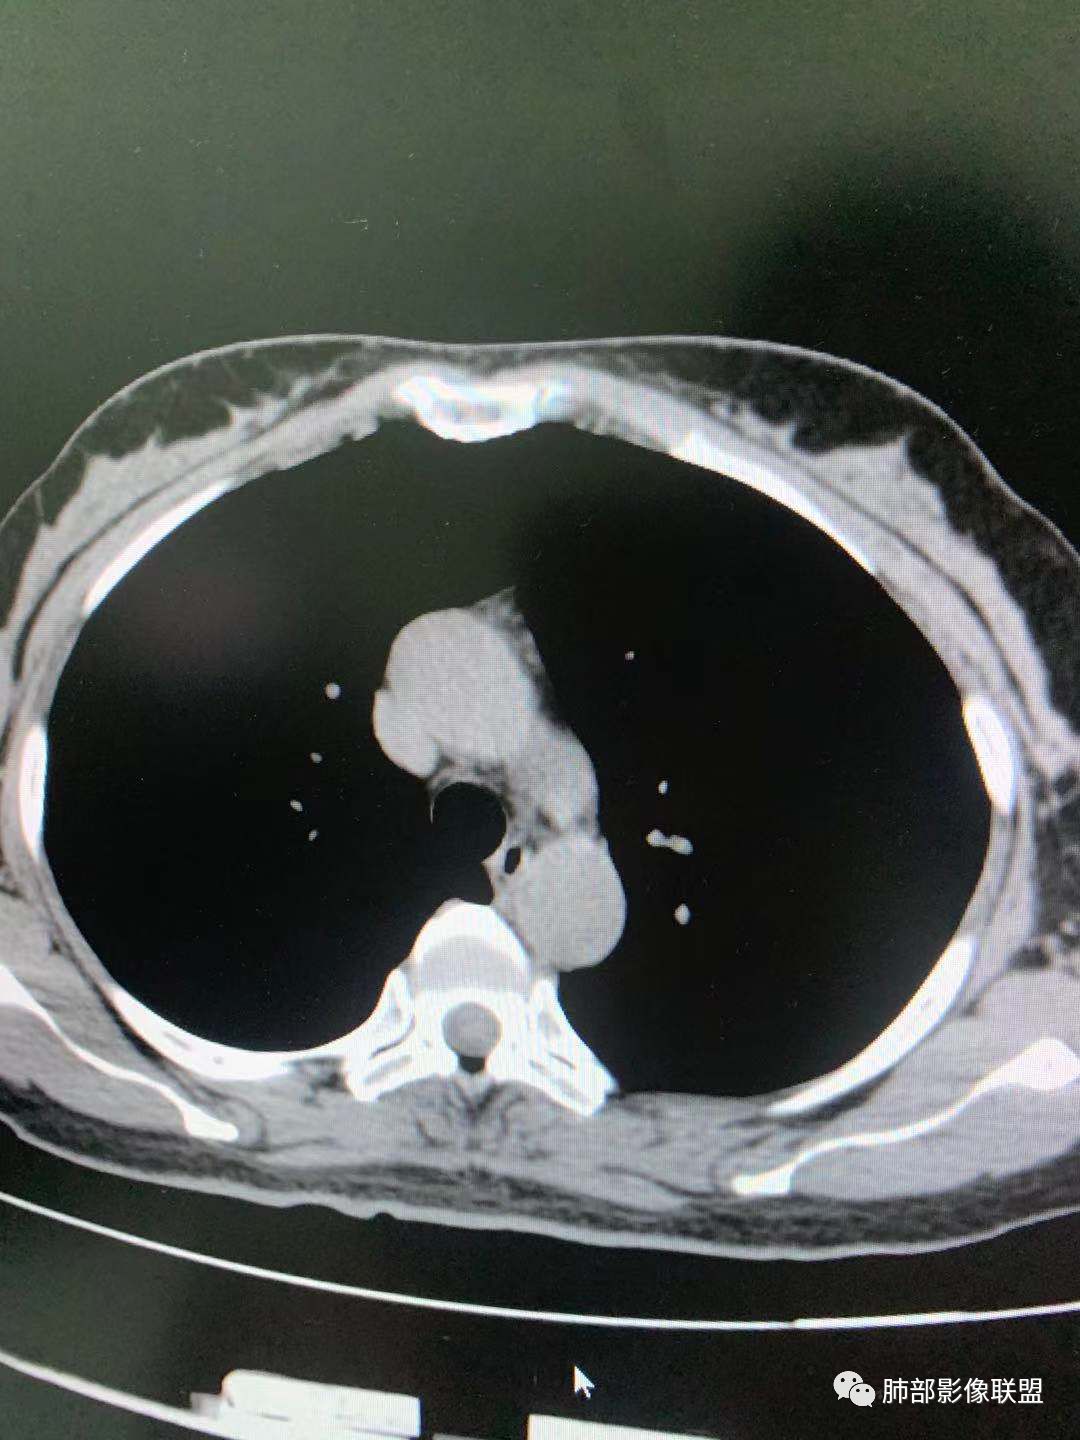

一.尖后段高密度大结节:

1.左肺上叶尖后段较大类圆形实性密度结节影,密度均匀,中等程度强化。

2.实性密度区边缘相当清楚,表面欠光整,偶见毛刺、棘突和旁出血管结构,未见典型的深分叶及邻近胸膜凹陷。

3.可疑支气管进入受阻。可惜缺乏连贯图像或冠矢状位以资判断。

4.病灶与胸膜之间有连线,邻近段支气管及肺血管整体后移,提示病灶还是有一定收缩性。

如上,单就这实性结节,硬化性肺细胞瘤(PSP)和腺癌似乎都能够解释,形态太规整了一些。

5.病灶周围见边界清楚的磨玻璃影,有点醒目,有点意外!

这是无论如何不能忽视的征象!

这点强烈提示,要么整个病灶恶性(腺癌),要么良性病灶旁滋生恶性病灶。

两年前左上肺的病灶什么位置,什么模样,是否相关?我们不得而知。